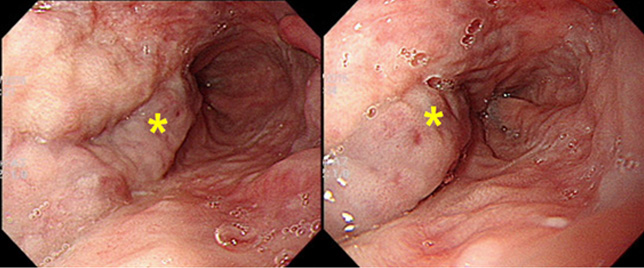

- 합병증은 식도, 위 정맥류 출혈, 간경변성 복수, 간성뇌증, 간신증후군, 간암의 발생이 있습니다.

- 우리나라의 연도별 간세포암종 발생건수 및 발생률

- 위험요인으로 B,C형 만성간염자, 알코올, 흡연등이 잘알려져 있습니다. 특히 간염 바이러스는 간암의 가장 중요한 원인으로 알려져 있으며, B,C 형 간염이 전체 간암 발생의 75~80%정도 중요합니다. 따라서 B,C형 만성 간염이 있는 위험군 환자들은 조기진단을 위한 정기적인 진찰 및 검사가 필요합니다.

- 진단을 위해 필요한 검사는 간초음파, 간복부전산화단층촬영, 간 조영증강 MRI, 혈관조영술, 간조직검사, 암 표지자로서 알파태아단백(aFP)이 있습니다.

- 치료는 병기에 따라, 환자 상태에 따라 다양한 방법이 있습니다. 수술적 방법으로 간절제술, 간이식이 있으며, 국소치료술로 고주파열치료술, 에탄올주입술이 있으며, 그 외 경동맥화학색전술, 체외 방사선치료, 전신 항암요법이 있습니다. 이는 환자 상태 및 병기에 따라 선택되어 시행할 수 있습니다.